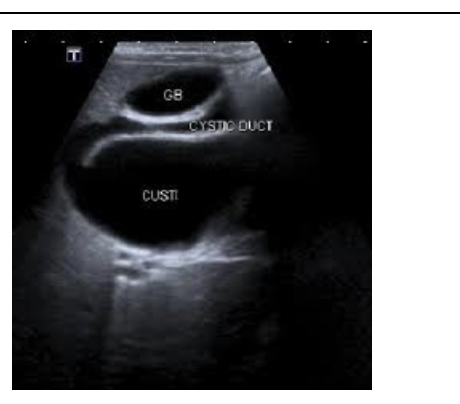

What Pathology is in the image below

Distention/Hydrops - enlarged gallblader intravenous